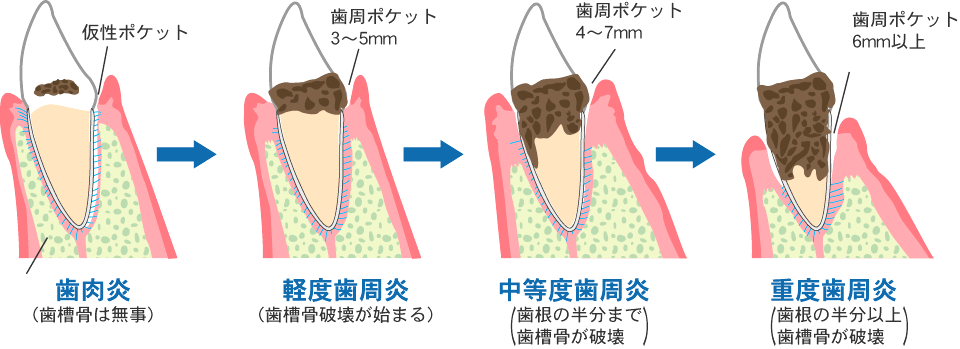

一般的な歯周病治療では、まず歯周ポケット(歯と歯茎の間の溝)の深さを正確に測定します。歯周ポケットの深さや歯石の程度、歯茎の状態によって、各ステージに合わせた処置や治療法が選択されます。

歯のクリーニング(軽度歯周病の患者さま)

軽度歯周病と判断できる場合は、歯のクリーニングのみで治療は完了します。

ルートプレーニング(中度歯周病の患者さま)

ルートプレーニングとは、特殊な器具で歯周ポケットの奥にこびりついた歯石や汚れを除去する方法です。

中度歯周病の場合、ある程度の深さにまで歯石が食い込んでいきますので、器具を入れ込む関係上、治療時には出血が伴い痛みも想定されます。

外科処置や歯周再生療法(重度歯周病の患者さま)

歯周病が重度にまで進んでしまうと、ルートプレーニングでは届かない位置にまで歯石が付着してしまいます。このような場合には、麻酔をかけ、外科的に歯茎の一部を切開し、歯の根元部分から歯石を完全に除去します。この後に、再び歯茎を縫合するという方法を取ります。場合により、歯周再生療法(エムドゲイン)と呼ばれる、なくなってしまった歯肉周辺組織を再生させる治療を行うこともあります。

従来、中等度歯周病以上(歯周ポケット4mm以上)の治療では、歯周外科といってメスを使用して歯ぐきを剥離して歯石を除去した後に歯ぐきを縫う方法や、一度抜歯して歯面に付着した感染組織を除去後、再度植立させるような負担の大きな手術を必要とする歯石除去法しかありませんでした。

しかし、近年ではマイクロスコープと小型の清掃器具を併用することにより、歯ぐきを切ったり、痛みを伴ったりすることなく、歯周ポケットの奥深くに付着した歯石の確認、除去が可能となりました。患者さまの負担を抑えながら、より効率よく歯周病の改善が期待できます。